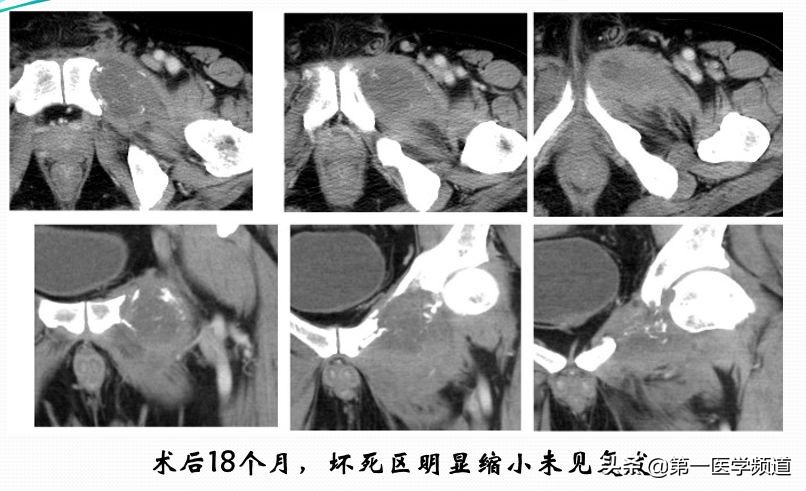

这是一个肝癌骨转移的病人。临床上病人骨质有明显的破坏,造成了下肢行动障碍,疼痛非常显著。做了完全性的冷冻消融,整个肿瘤凝固性坏死。临床上,对病人来说,疼痛的缓解非常明显,术后18个月坏死组织明显地缩小,也未见肿瘤的复发,肿瘤病灶完全坏死。